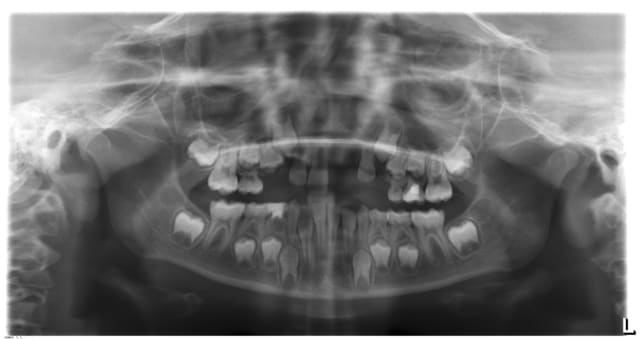

je vous soumet le cas de ma petite patiente 7 ans, il y a trois mois environ elle a été victime d'un accident de la circulation.

la 21 a été expulsée et perdue, et la je sèche.... que faire?

ça ne répond pas à la question mais y'a pas aussi un problème d'espace au niveau 13/14 à prendre en compte?

J'attendrai l'éruption des canines permanentes avant d'envisager un bridge collé. Pour le moment, je ferai un arc palatin avec 2 bagues scellées sur les 6 et une dent prothétique.

merci pour vos approches, ça m'aide beaucoup, je posterai une photo, je la revoie à la rentrée, je pense que je vais opté pour la solution de Tigabi dans premier temps, les autres incisives sont en cours d'éruption, le cantilever viendra plus tard.